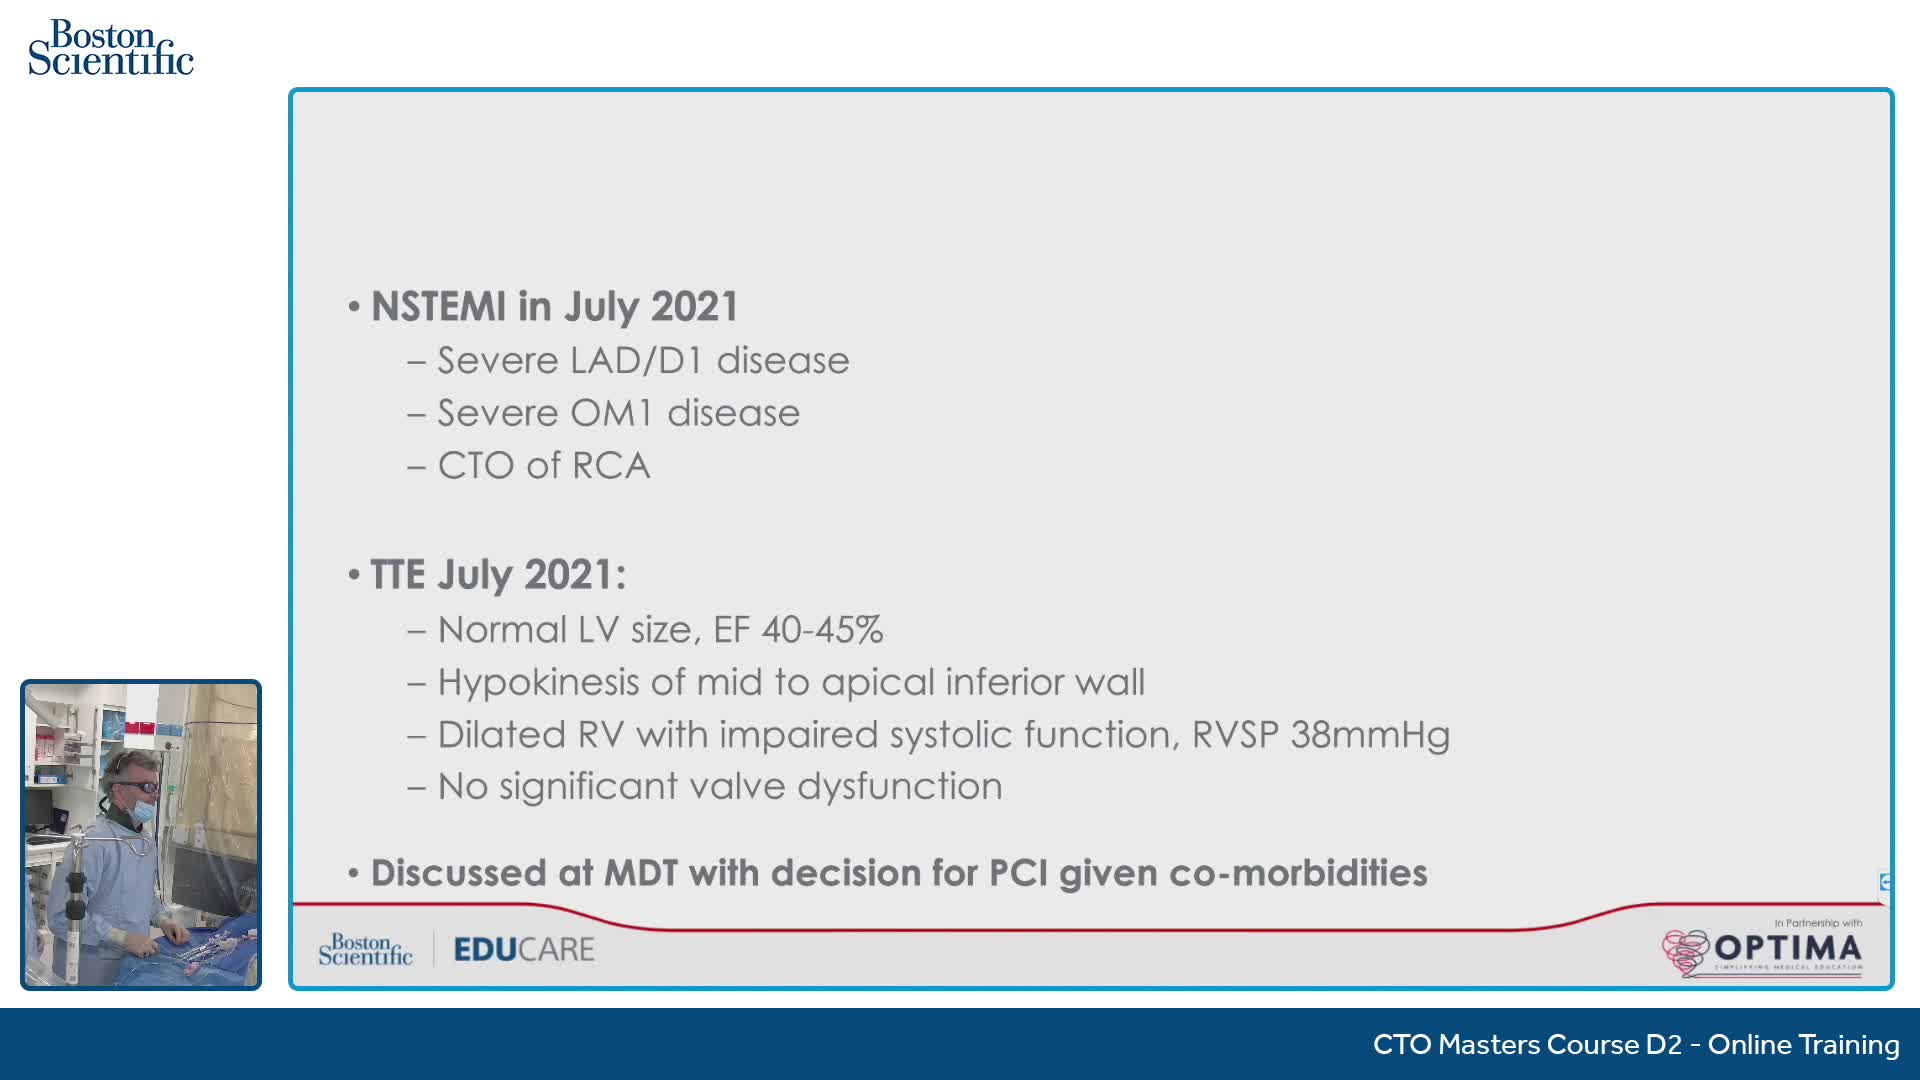

Gulf-Optimal Chronic Total Occlusion: Live Case Follow Up